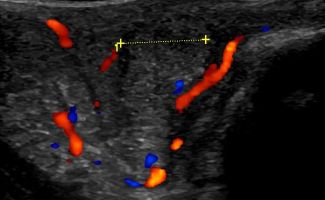

Πολλές αλλοιώσεις και παθήσεις μπορούν να απεικονιστούν υπερηχογραφικά και να μελετηθούν αξιόπιστα με τη βοήθεια του Έγχρωμου Doppler και της Ελαστογραφίας .

- Αιμαγγειώματα, αγγειοδυσπλασίες (αγγειακού τύπου βλάβες)